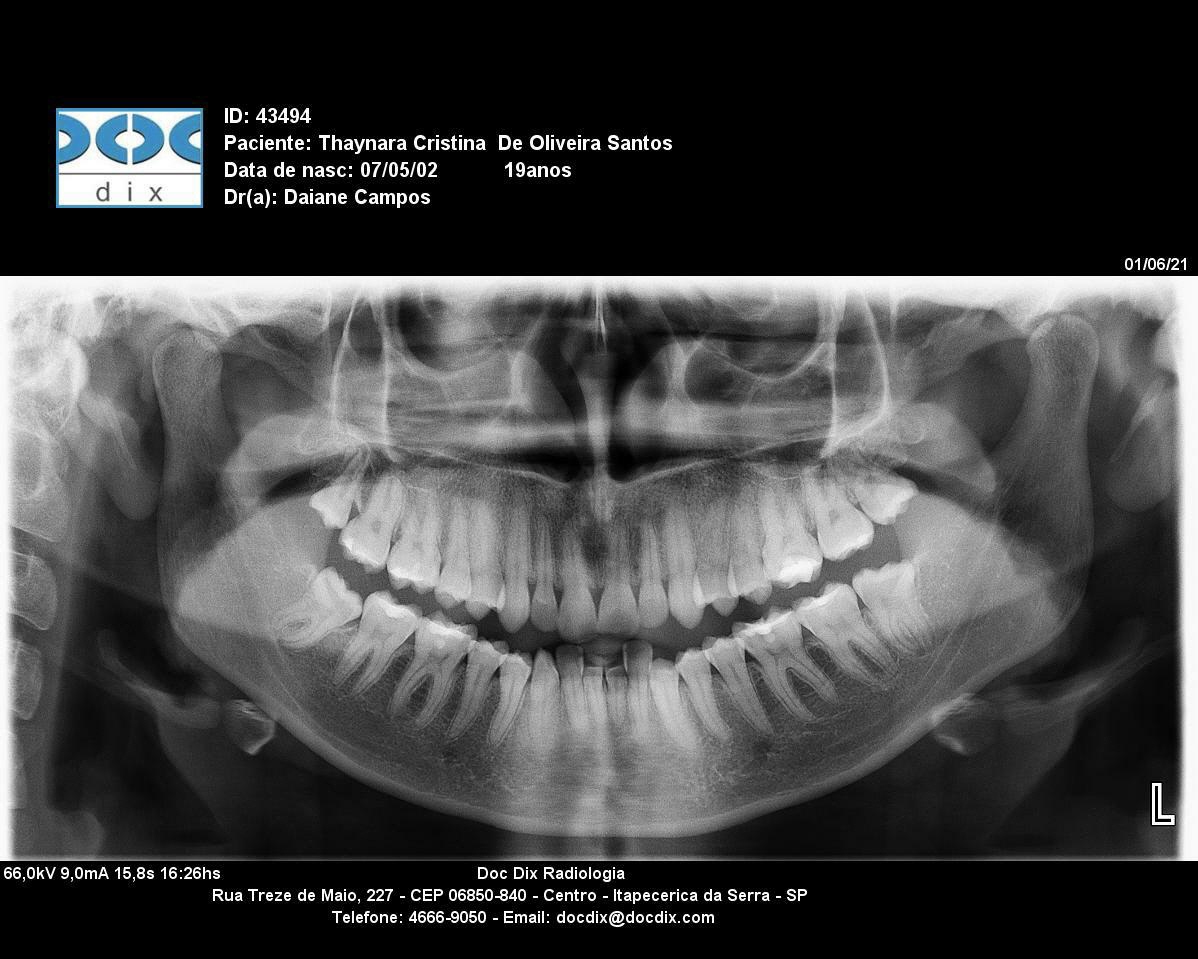

Data do exame: 01/06/2021

Laudo Radiográfico

Tipo de dentição

Dentição permanente - Nenhum elemento ausente.

Nenhum elemento Extranumerário.

Detalhamento dos achados

Dentes 18, 38 e 48: semi irrompido.

Demais estruturas preservadas.